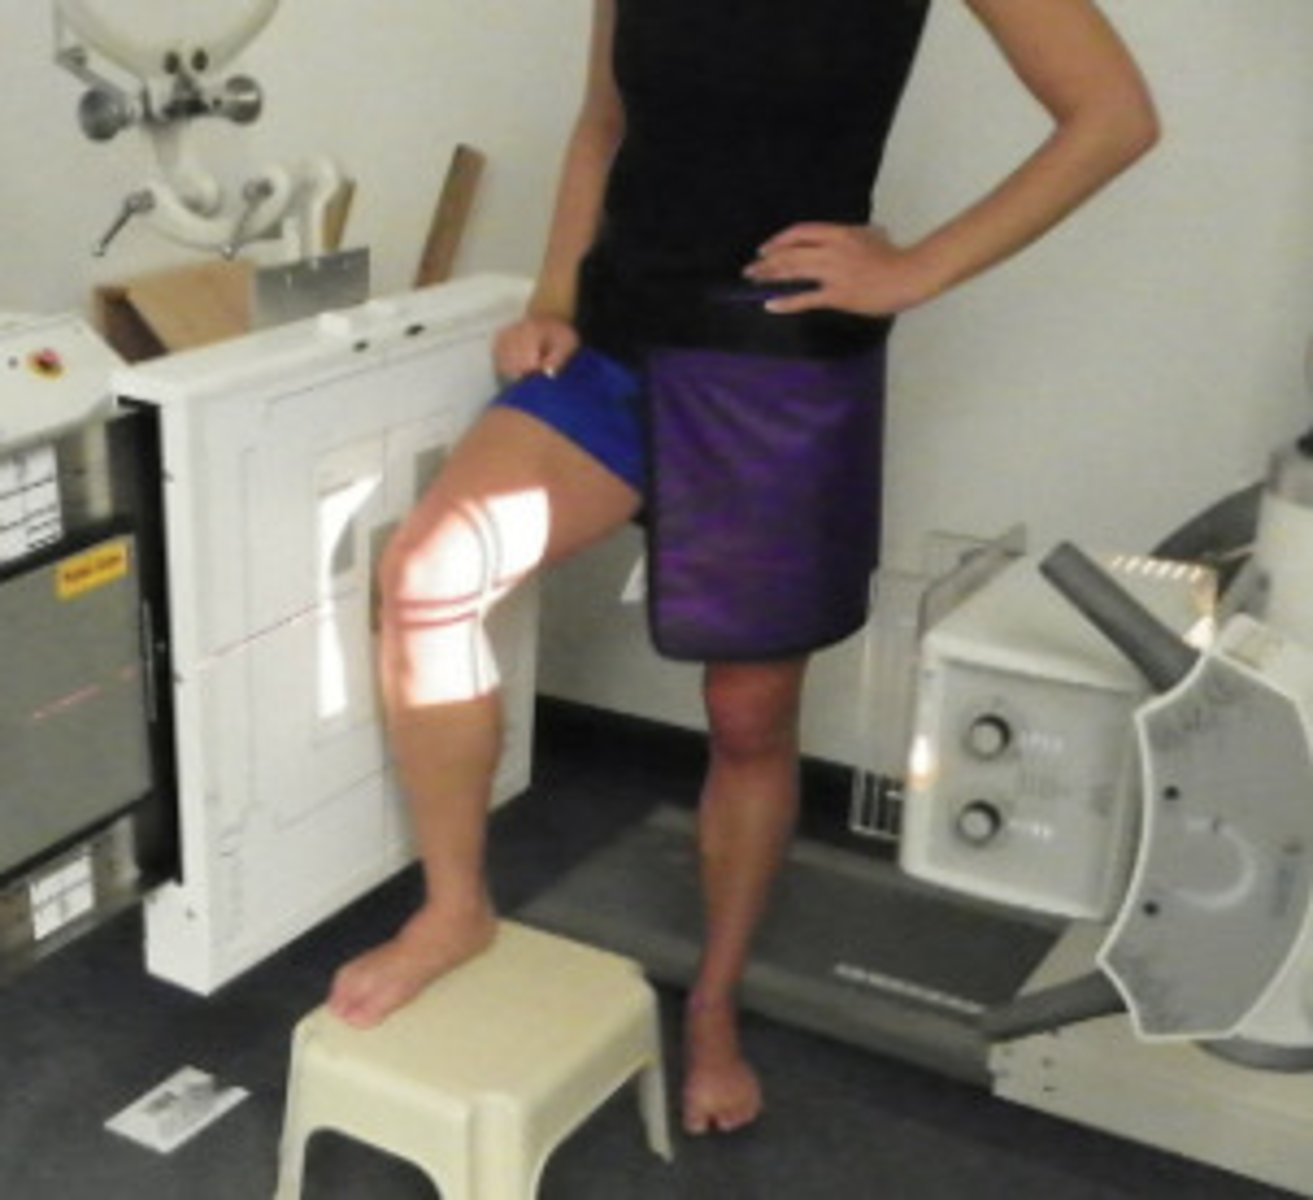

Describe, in detail, how a PATIENT should be positioned for a ROSENBERG KNEE projection.

1. The patient is weight-bearing in a PA position; patient to stand on a stool against the bucky.

2. Tibia should be touching & parallel with the IR.

3. Rotate lower leg to ensure centralisation of the patella.

4. Patient to hold the bucky column and then sit/squat back. Encourage weight distribution to the joint being imaged.